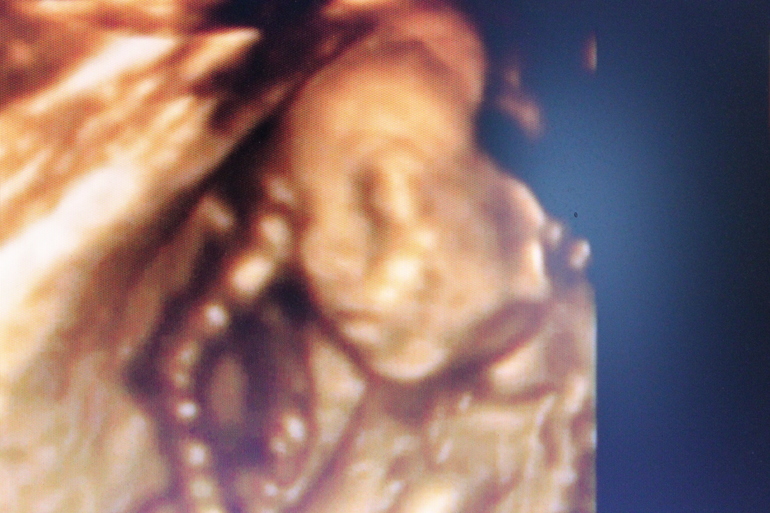

А сегодня прям сразу начали личико показывать, а я такая в лоб: нас больше интересует, что там пониже)))))

В начале мы его разбудили и он все время открывал ротик, зевал))

И вообще, хорошенький такой, у меня прям слезы текли)))))))